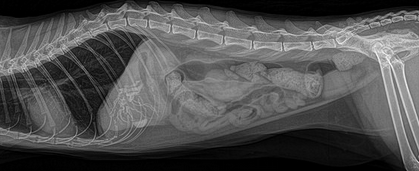

La photo montre une radiographie d'une occlusion intestinale chez un chat.

Important ! Une radiographie peut confirmer le diagnostic. Comme vous pouvez l’imaginer, il est impossible de réaliser cet examen à domicile, même si vous constatez des symptômes d’occlusion intestinale chez votre chat. Pour aider votre animal, vous devez contacter un vétérinaire immédiatement. N'attendez pas pour consulter un vétérinaire, sinon votre animal pourrait mourir. L'automédication est non seulement inefficace, mais aussi dangereuse.